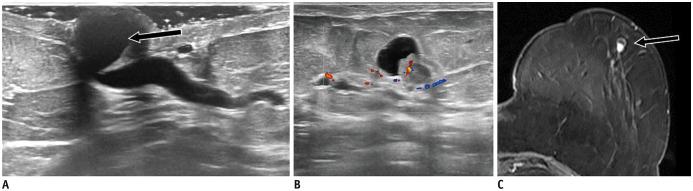

Ultrasound (US) is an attractive diagnostic approach to identify both common and uncommon nipple pathologies, such as duct ectasia, nipple abscess, nipple leiomyoma, nipple adenoma, fibroepithelial polyp, ductal carcinoma (restricted to nipple), invasive carcinoma, and Paget's disease. US is the reliable first-line imaging technique to assess nipple pathologies. It is useful to identify and characterize nipple lesions. Additionally, we have presented the mammography and MRI outcomes correlated with histopathologic features for the relevant cases.